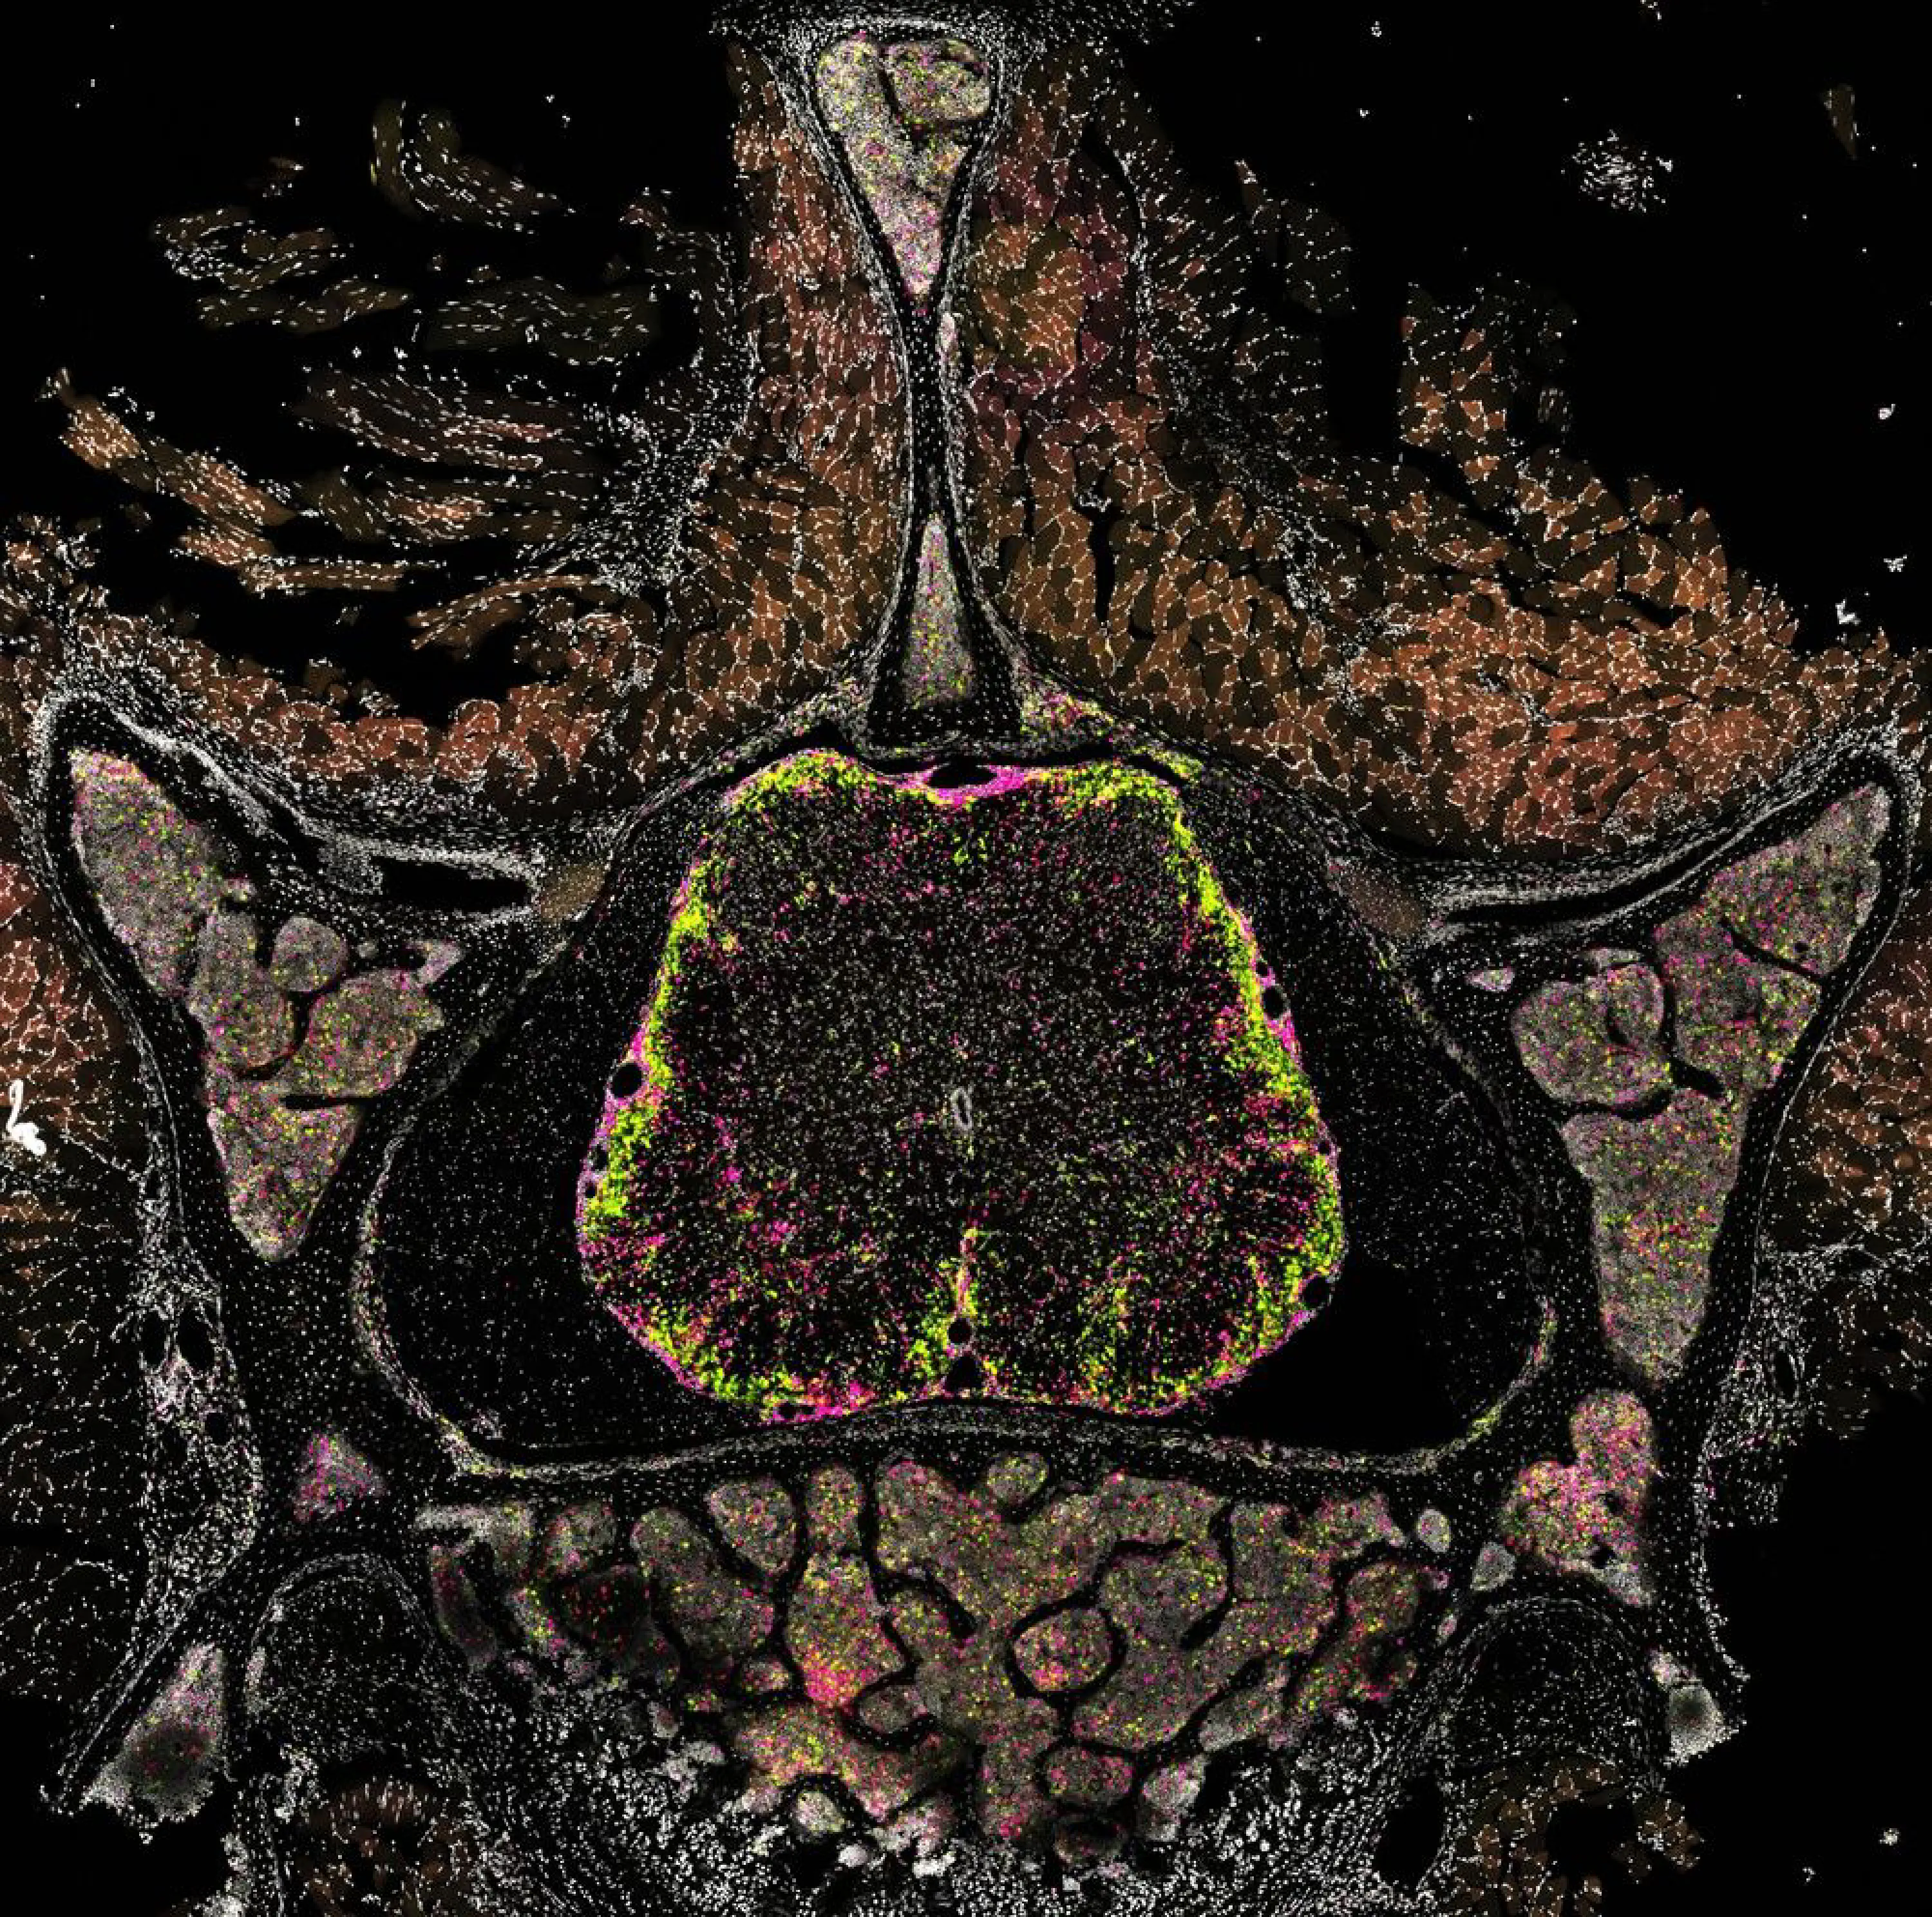

In this work, Clara de la Rosa et al. established an in vivo CRISPR screening pipeline using genetically editable progenitor cells to dissect macrophage regulation in mouse models of multiple sclerosis (MS). Screening over 100 cytokine receptors and signaling molecules identified interferon-γ, tumor necrosis factor, granulocyte-macrophage colony-stimulating factor and transforming growth factor-β as essential regulators of macrophage polarization in vivo. Single-cell transcriptomics confirmed that transferred progenitor cells generate all blood-derived CNS myeloid cell populations, enabling Perturb-seq analysis of cytokine actions in neuroinflammation. Combined with biosensor expression, this approach allows monitoring cytokine effects on myeloid cell migration, debris phagocytosis and oxidative activity in vivo. Comparative transcriptomic analyses revealed conserved neuroinflammatory cytokine signatures across myeloid populations, CNS compartments and species, elucidating cytokine cues shaping myeloid function in the cerebrospinal fluid and parenchyma of individuals with MS. This versatile pipeline thus provides a scalable framework for high-resolution analysis of macrophage states and uncovers the cytokine signals that underlie their regulation in MS and MS models.

© Kerschensteiner Lab